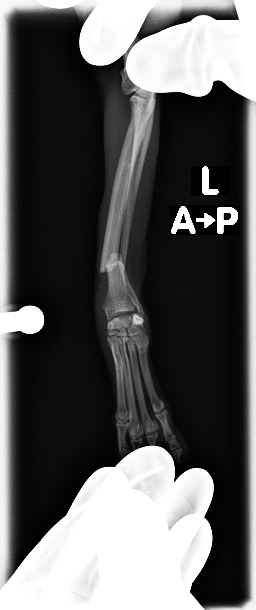

左前肢、橈骨、尺骨骨折

before